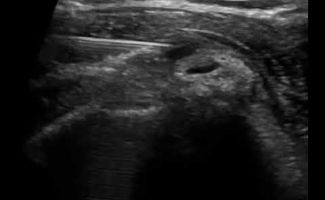

Although the initial diagnosis of Calcific Tendonitis can be made with a simple shoulder X-ray, ultrasound imaging is the recommended method for visualizing calcifications. It provides detailed information about their size, location, and stage.

When calcifications are in the resorption stage, they can be visualized with ultrasound but may not appear on a standard X-ray. Additionally, ultrasound allows for the study of tendons to determine if there are other issues, such as tendon tears.